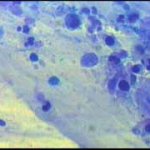

Ατυπα κύτταρα ενδοτραχήλου, άμεση χρώση με bleu de methylen 0,25% μεγεθ. 10Χ40. Αδενοκαρκίνωμα ενδοτραχήλου - ενδομητρίου

Ατυπα κύτταρα ενδοτραχήλου, άμεση χρώση με bleu de methylen 0,25% μεγεθ. 10Χ40. Αδενοκαρκίνωμα ενδοτραχήλου - ενδομητρίου